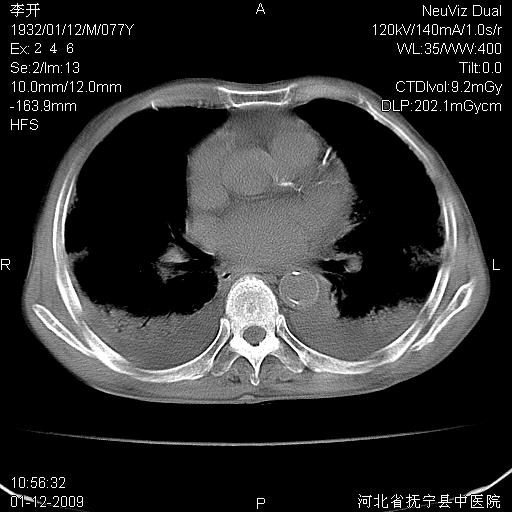

以下是引用黑白光影在2009-1-19 16:49:00的发言:[br]心衰肺水肿;心包、胸腔积液;冠脉钙化;肺部感染。